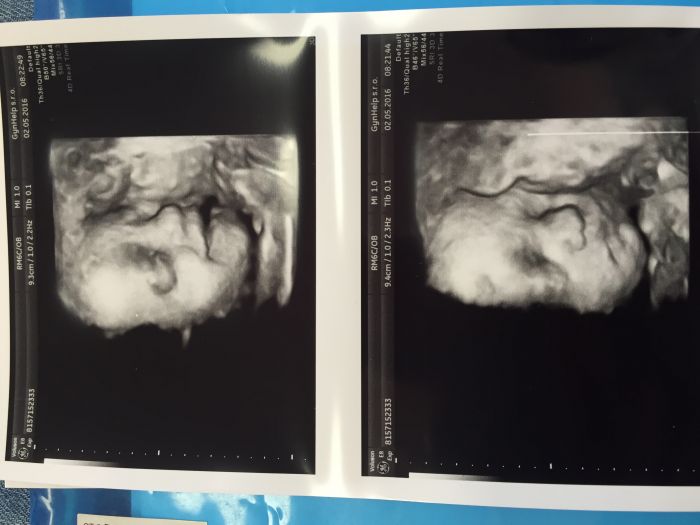

Ahoj holky, tak ja dnes na UZ. Uz nam krasne rostou. Kdy planujete, ze pujdete na materskou? Mne to vychazi na zac. Cervna, coz je uz za mesic, ale citim se porad ok, mam nahore jen 5 kg, tak se mi jeste moc nechce.